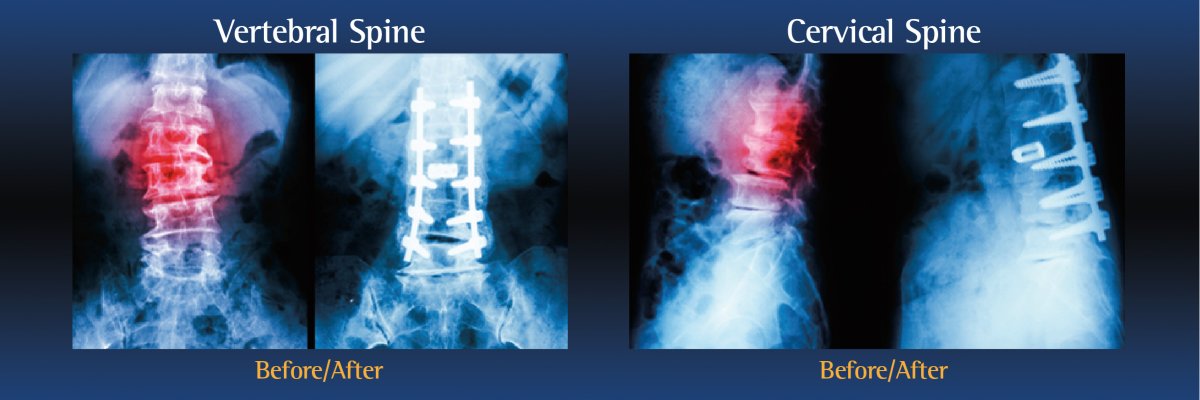

Types of spinal fusion surgery

There are several types of spinal fusion surgery. The type of procedure performed will depend on the patient’s individual condition, as well as the location of the pain:

- Cervical Fusion is performed on the neck

- Lumbar Fusion is performed on the lower back

During the operation, an incision is made in the neck, back or abdomen. Bone, debris, bone growths, lamina, and/or the damaged vertebral disc may be cleared from the spine, creating more space and relieving pressure on the spinal nerves. The surgeon will then take the proper steps to correct the patient’s specific problem.

Bone grafts may then be placed in the space or along the side of the spine. If additional support is needed, metal hardware (including pins or screws), may be used to steady the spine as it fuses. The incision is closed to finalize the surgery.

The grafts will grow into solid bone, fusing together the vertebrae. Patients may have to wear a back brace post-surgery, which will support your spine and keep the vertebrae from moving as the grafts fuse together.